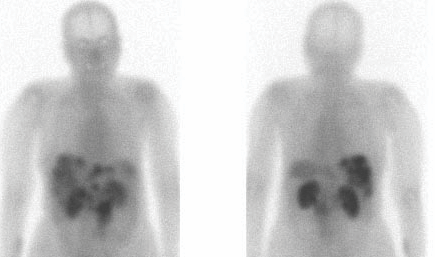

The efficacy of 68Ga-DOTA-TATE in assessing this kind of tumors has been proved by numerous studies.

• Patients with suspected or proven tumors expressing Somatostatin receptors